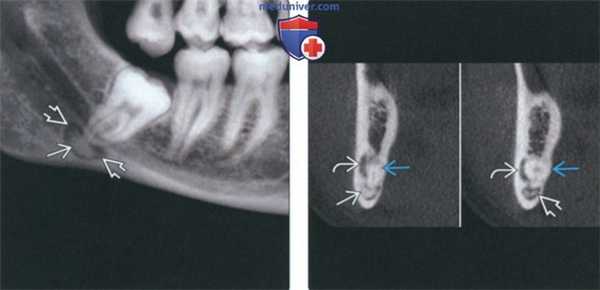

(Слева) На панорамной реформатированной КЛКТ определяется очаг смешанной плотности, образованный мелкими структурами, напоминающими зубы окруженный рентгенонегативным «ободком» и кортикальной пластинкой. Это составная одонтома - самая частая одонтогенная опухоль.

(Справа) На кадрированной панорамной рентгенограмме определяется однородный рентгеноконтрастный очаг, окруженный рентгенонегативным «ободком», связанный с мезиальным корнем второго временного моляра нижней челюсти справа и приводящий к его резорбции. Эта цементобластома смещает второй премоляр. (Слева) На окклюзионной рентгенограмме определяется экспансивный рентгеноконтрастный очаг однородной структуры с рентгенонегативным «ободком». Корни клыка и первого премоляра нижней челюсти слева изогнуты в язычную сторону в результате воздействия этой цементооссифицирующей фибромы.

(Справа) На кадрированной панорамной рентгенограмме визуализируется хорошо отграниченный очаг смешанной плотности, который был ошибочно принят за цементобластому, несмотря на наличие выраженной болевой симптоматики и отсутствие фиксации к корню зуба.